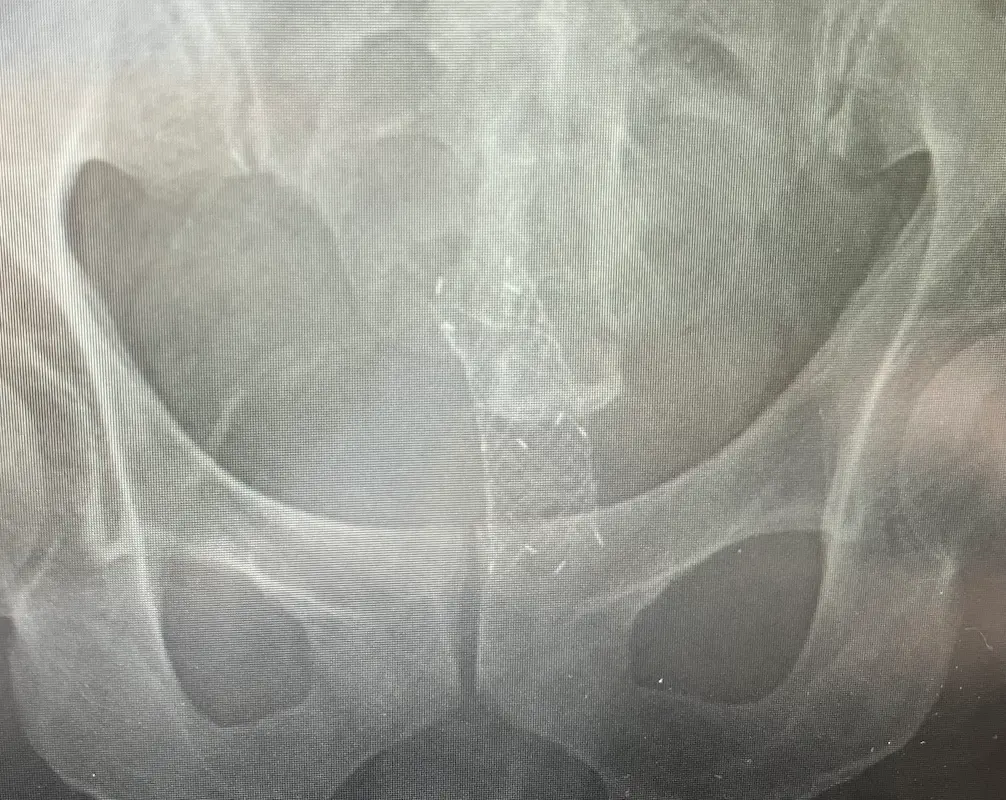

2025年4月:レントゲン検査

ステントが順調に広がっているかを確認するためにレントゲンで検査。無事に広がっていました。

2025年11月:ステントが行方不明に

4月に大腸に挿入手術したステントが先月から行方不明になっています。10月に撮影したレントゲンやCTで確認できないのです。

がんが縮小したのであればいいのですが、何らかの理由でステントが緩み、便と共に排出してしまったよう。確かにここ最近、便の出にくさを感じていました。